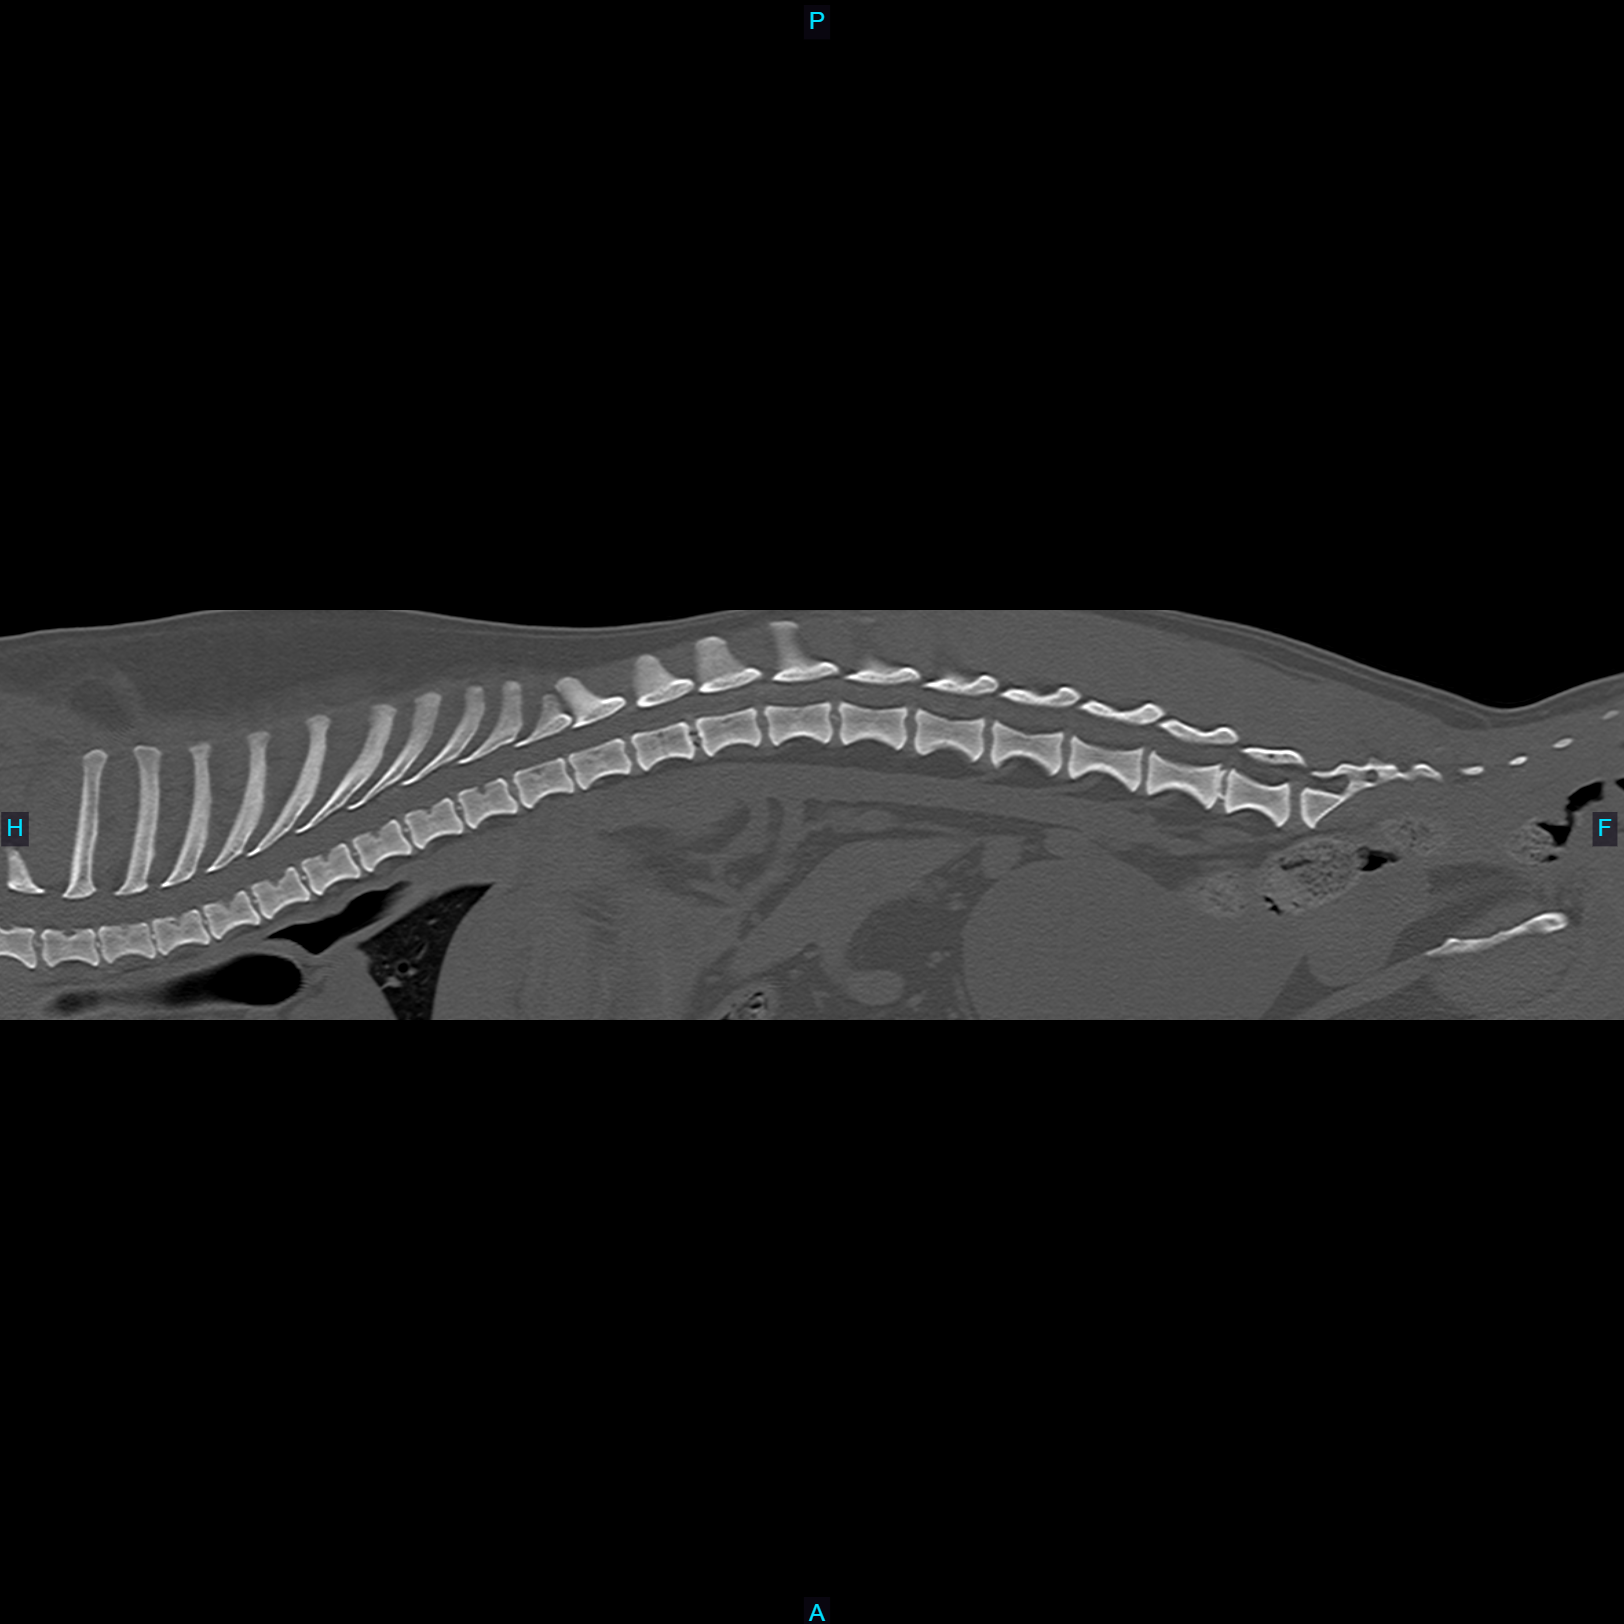

Computed Tomography (CT), also known as a CAT scan, is an advanced imaging technique that combines X-ray technology with computer processing to generate detailed cross-sectional images of an animal's internal structures.

The animal is typically sedated or anesthetized to remain still during the procedure, ensuring high-quality images. Special positioning aids may be used to maintain the correct posture. The animal is placed on a motorized table that moves through a circular opening of the CT scanner. The scanner consists of an X-ray tube that rotates around the animal, emitting X-rays from different angles. Veterinarians and veterinary radiologists analyze the CT images to identify abnormalities such as tumors, fractures, organ diseases, and other conditions. The high-resolution images allow for a detailed examination that is often not possible with traditional X-rays.

- Evaluating complex fractures, joint abnormalities, and spinal disorders.